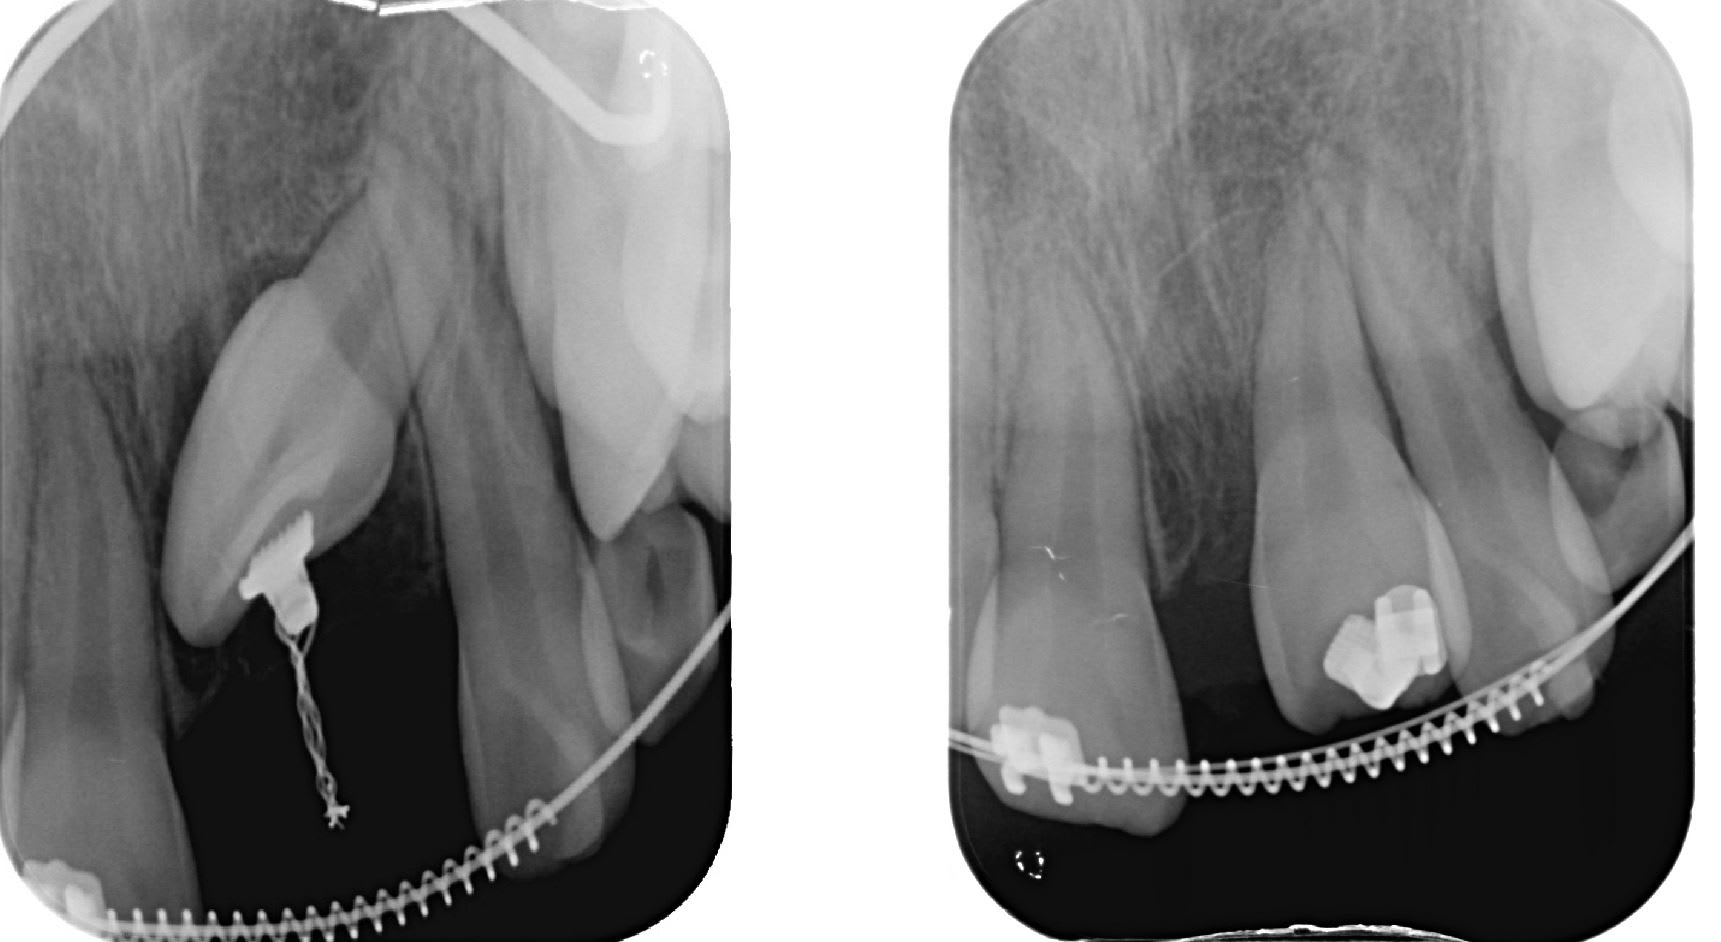

Un cas équivalent. Regarde la position foireuse de la racine.

Juste en realisant une traction j'ai peut tout corriger dans le même temps par tipping ( rétro confirmant l'alignement des racine ).

J'ai pas la derniére pano sur mon portable, mais toute les racines sont parrallée. Et ça c'est fait en quatre mois.